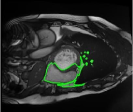

4.3 Comparison with cardic MR images for right ventricle segmentation

Cardiac MRI images often suffer from intensity inhomogeneity due to the varying magnetic susceptibility of cardiac tissues. This can lead to ambiguous boundaries, making it hard for models to consistently identify the left ventricle. Moreover, the heart is composed of several complex anatomical structures, including chambers, valves, and surrounding tissues. Accurately delineating the borders between these various components can be difficult, especially when they are closely positioned or exhibit similar intensity characteristics. In this section, we demonstrate the effectiveness of the RefLSM in segmenting cardiac MR images. The cardiac MR images are standardized to a size of . To enhance the credibility of the proposed model, we segmented 5 cardiac MR images compared the results with 6 other models, including the ALF [MA2019201], LoGRSF [DING2017224], ABC [WENG2021115633], RESLS[8765635], ICTM [WANG2022108794] and FeaACM [XUE2024110673] models. Fig. 5 displays the partial results from all the segmentation models. It is clear that the segmentation results from the RefLSM closely align with the ground truth of the left ventricle segmentation. However, the ALF model demonstrates relatively poor ability to capture the overall structure of the left ventricle; it exhibits limitations with precise boundary detection, particularly in areas of intensity inhomogeneity. Consequently, the evolution curve of the ALF fits into an unstable wave-like result. Suffering from intensity inhomogeneity and surrounding anatomical structures, the LoGRSF model, ABC model and RESLS model all represent over-segmentation and under-segmentation to some extent. Additionally, the results in the 6th column of Fig. 5 show multiple instances where where the ICTM model inaccurately identifies adjacent myocardial tissues as part of the left ventricle due to their similar intensity, leading to false positives. While the FeaACM demonstrates some ability to segment the left ventricle, it is not robust and fails to segment the 5th row of Fig. 5. The 2nd and 3rd rows also include small adjacent excessive regions. In contrast, our proposed model demonstrates marked improvements in accurately capturing the left ventricle’s boundaries. It effectively addresses challenges associated with severe intensity inhomogeneity and noise, resulting in better segmentations. The proposed method appear to maintain better structural integrity in the segmented images, closely aligning with the ground truth.

To quantitatively measure the segmentation results of each model, we compute the Dice and Precision values for left ventricle segmentation. Moreover, we opted for a voilin plot to effectively compare the RefLSM with six other models, as shown in Fig. 7. The results clearly demonstrate that the RefLSM yields superior Dice and Precision values than the other representative models, indicating its closer alignment with the ground truth and highest segmentation accuracy.